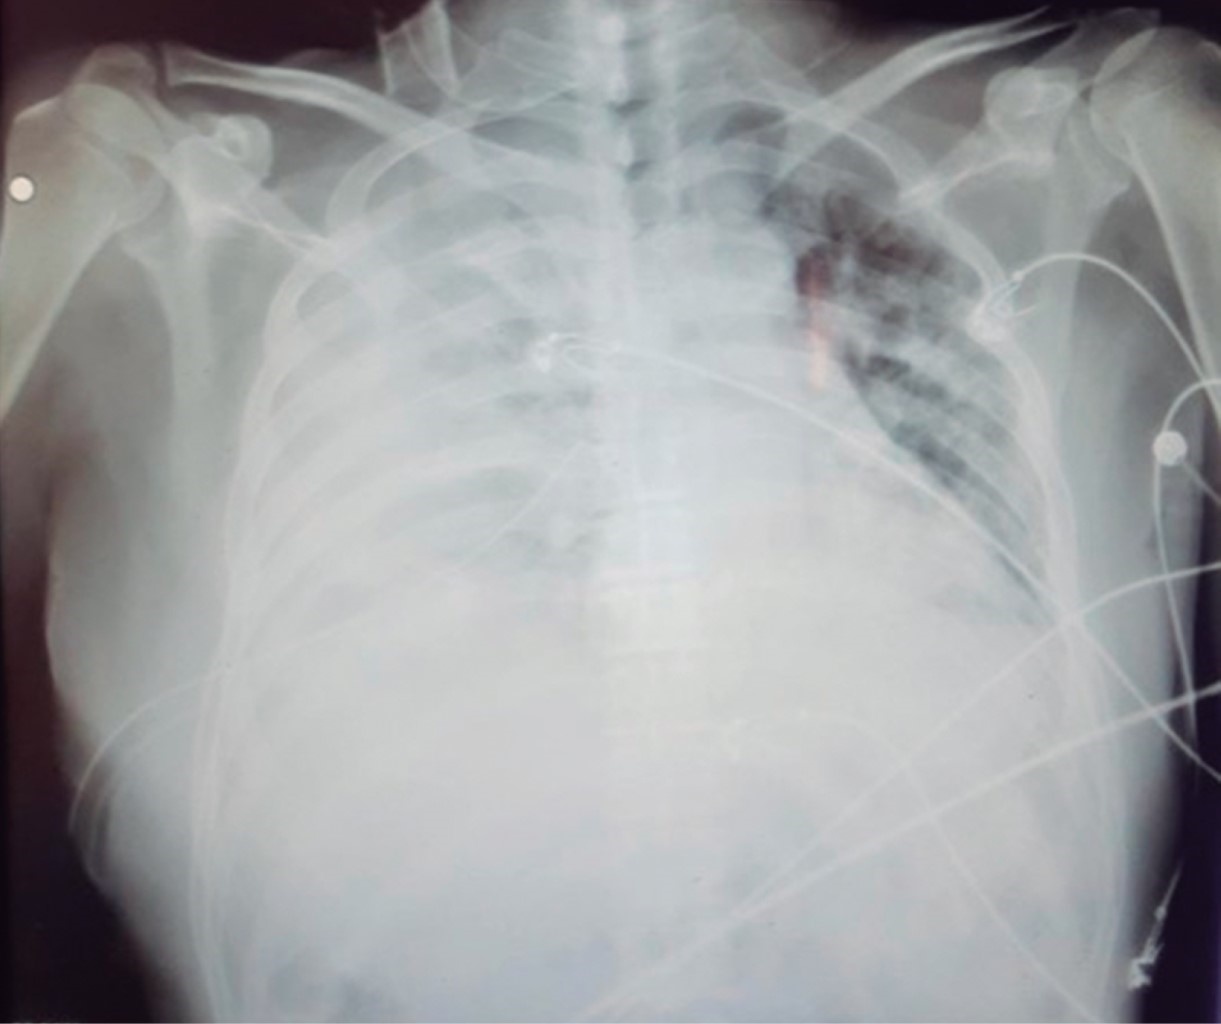

Es extubado el 28-05-20, posterior a ello el paciente presenta un derrame pleural derecho de 80%, por lo que se interconsulta al servicio de cirugía general el 05-06-20 para colocación de sonda endopleural (Figura 1).

Figura 1